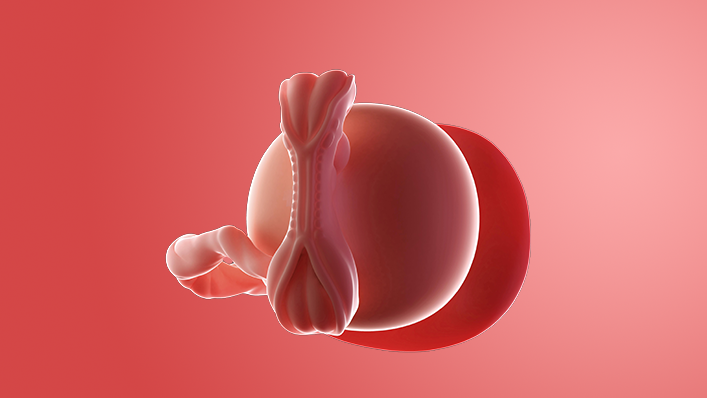

What does my baby look like?

Your baby, or embryo, is around 6mm long, which is about the size and shape of a pea. Some people think it resembles a tadpole with its little tail.

The arms and legs are starting to form and are known as limb buds. There are tiny dents where the ears will be.

There's a bump where the heart is and another bulge where the head will be. Sometimes the heartbeat can be picked up by a vaginal ultrasound scan, but you are unlikely to be offered one unless you've had IVF.

The embryo is covered with a thin layer of transparent skin.